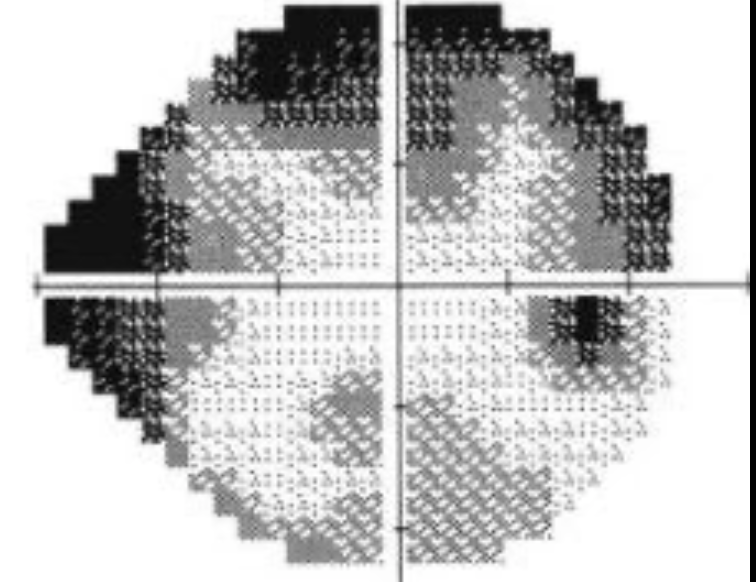

Como apresenta-se no campo visual o excesso de falso negativos?

Trevo de 4 folhas

Tons de cinza - Gráfico em escala de cinza que deriva do gráfico numérico. Quanto menor a sensibilidade, mais escuro o tom

O que representa o gráfico total deviation?

Sensibilidade ponto a ponto do paciente - Sensibilidade esperada para indivíduos normais da mesma idade (baseado no banco de dados do aparelho)

Áreas com defeito de campo apresentam valores negativos

O gráfico total deviaton gera um gráfico de probabilidades que mostra a chance daquele defeito encontrado ser encontrado em um indivíduo normal